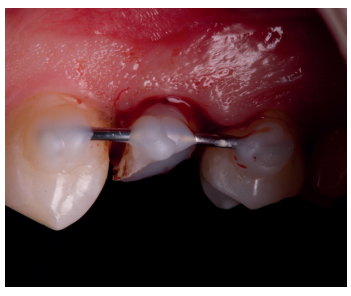

Una vez se hubo posicionado el diente 2 mm supragingival, se procedió a la ferulización con alambre de acero a los dientes adyacentes (Figuras 3 y 4) y la eliminación de cualquier tipo de oclusión, utilizando topes oclusales en los segundos molares inferiores. La ferulización se mantuvo durante dos semanas, coincidiendo con el momento de la endodoncia (Figura 5). El paciente fue citado para las revisiones periódicas y posteriormente para la rehabilitación del diente, una vez hubieron concurrido 6 semanas desde la extrusión, en las que se haya obtenido una cicatrización de los tejidos de soporte supracrestales10. En este momento, tras comprobar signos clínicos, periodontales y radiográficos saludables, se citó al paciente para el tallado y la confección mediante flujo digital (Cerec® System) de una endocorona de disilicato de litio (e.max®, Ivoclar Vivadent). El acondicionamiento de la corona se realizó con ácido fluorhídrico y silano, y para la cementación se utilizó cemento de resina (Calibra®, Dentsply Sirona).

adyacentes, tras la extrusión quirúrgica.